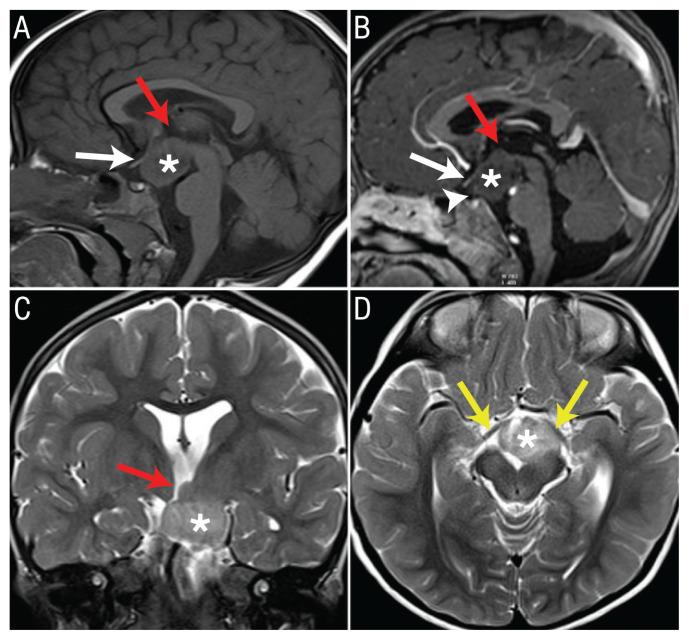

Inappropriate Laughter in a Patient with Hypothalamic Hamartoma.

Sultan Qaboos Univ Med J. 2020 May;20(2):e231-e233. doi: 10.18295/squmj.2020.20.02.016. Epub 2020 Jun 28.